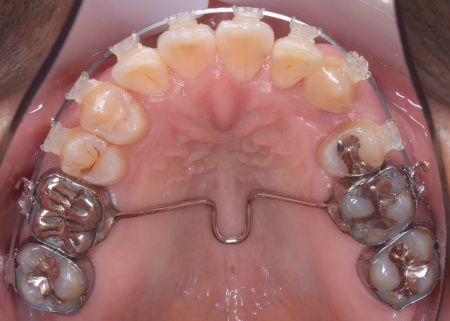

①抜歯をしてから歯並びを整える「抜歯矯正」 今回のケースでは、左上下の奥歯各1本(第3大臼歯)、右下の奥歯1本(第3大臼歯)、左上下と右下の奥歯各1本(第1小臼歯)の計6本の抜歯が必要です。 また、奥歯の噛み合わせは正常だったことから、それを維持しながら歯並びを整えるために以下の方法を採用します。 ②矯正治療後、歯周病を発症している左下奥歯(第1大臼歯)を温存するために、失われた骨や歯茎を再生する「歯周再生療法」を行う まずは歯の移動スペースを確保するために、計6本の歯を抜きます。 矯正治療終了後、歯の後戻りを防ぐため、上下前歯の裏側にワイヤーを接着して固定させる「フィックスリテーナー」を装着しています。 その後、左下奥歯に歯周再生療法を行って歯周病が改善したことを確認し、治療を終了しました。 |